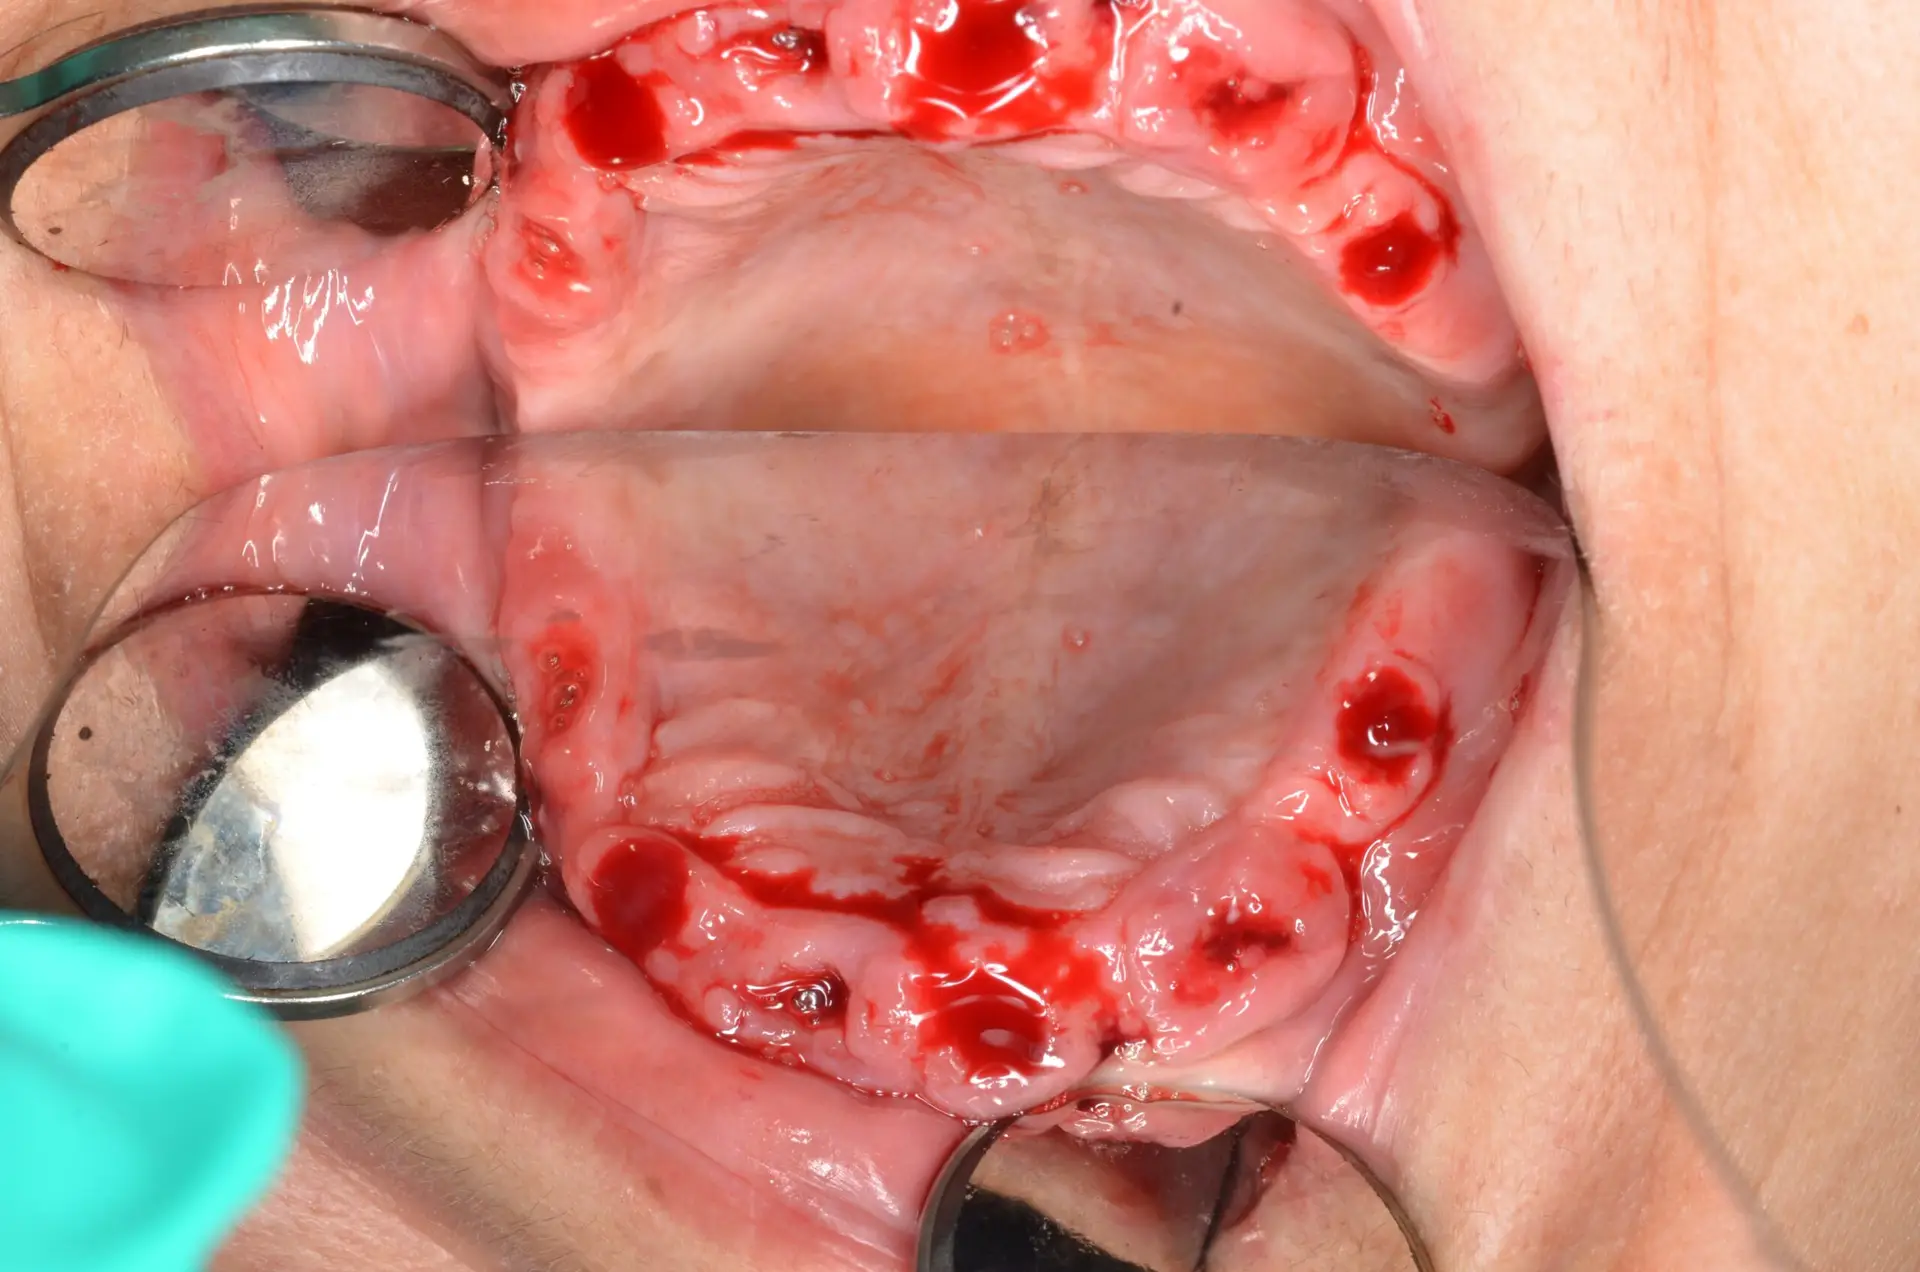

Documented case of Ana, a patient presenting with severe bone loss and failed implants. She was treated by our faculty member, Dr. Jay Neugarten, during the ZAGA Course as part of a live surgical demonstration for course participants. Treatment involved quad zygomatic implants and one pterygoid implant to improve stability. Using the ZAGA Approach, we were able to successfully rehabilitate the case despite the previous implant failures and deliver an immediate prosthesis on the same day as surgery. This case represents part of the clinical education and knowledge participants gain during the ZAGA course.